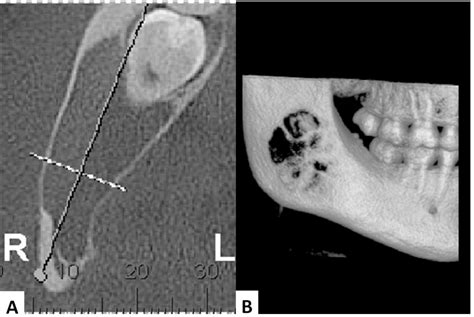

Diagnosis of a traumatic bone cyst typically involves a combination of clinical examination and radiographic imaging. Dental X-rays, such as periapical radiographs or panoramic radiographs, are commonly used to visualize the cyst. In some cases, a computed tomography (CT) scan or magnetic resonance imaging (MRI) may be recommended for a more detailed evaluation.

The radiographic appearance of a traumatic bone cyst can vary, but some common features include:

• Well-defined Radiolucent Lesion: The cyst appears as a well-defined, radiolucent area on dental radiographs.

• Scalloped Margins: The margins of the cyst may be scalloped, giving it a characteristic appearance.

• Cortical Bone Expansion: In some cases, the cyst may cause expansion of the cortical bone.

• No Internal Structures: Unlike other cysts, a traumatic bone cyst typically does not contain internal structures such as septa or calcifications.